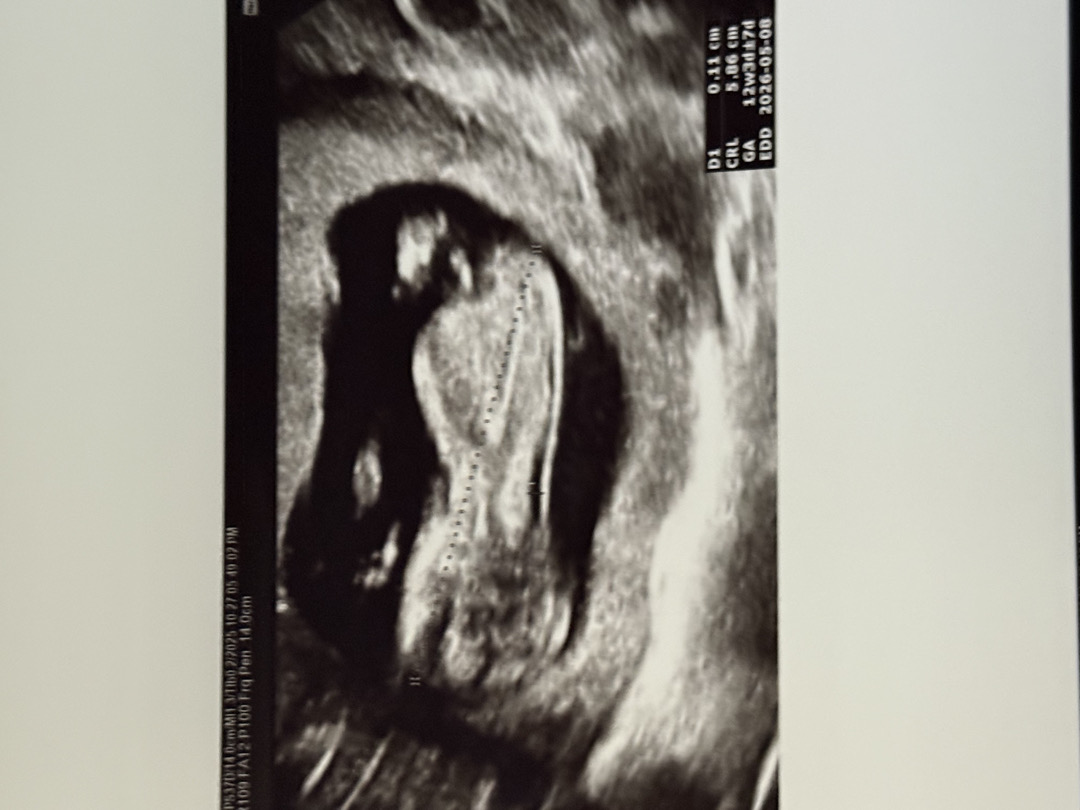

12주0일 입니당